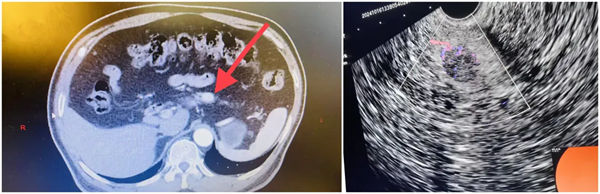

62歲的李女士反復出現腹脹、頭暈、心慌,曾在多家醫院就診,但一直未有明確診斷,后就診于市人民醫院肝膽胰脾外科,完善檢查后診斷為胰島細胞瘤。治療胰島細胞瘤的傳統方式是外科手術切除,但這兩名患者腫瘤位于胰腺實質內,定位困難,無法進行精準瘤體剔除,需要進行胰十二指腸切除或胰體尾切除術。但外科手術存在創傷大、恢復慢、并發癥多等缺點。

經過多次討論,評估患者各項檢查后,肝膽胰脾外科治療團隊綜合評估,考慮患者及家屬意見后,決定采用先進的超微創技術——超聲內鏡引導下瘤內無水酒精注射消融術進行瘤體精準治療。

超聲內鏡引導下胰腺神經內分泌腫瘤無水乙醇消融術依托先進的超聲內鏡設備,精準定位腫瘤位置,通過極細的穿刺針將無水乙醇直接注入腫瘤內部。無水乙醇能夠使腫瘤細胞迅速脫水、凝固,進而壞死,達到消除腫瘤的目的。